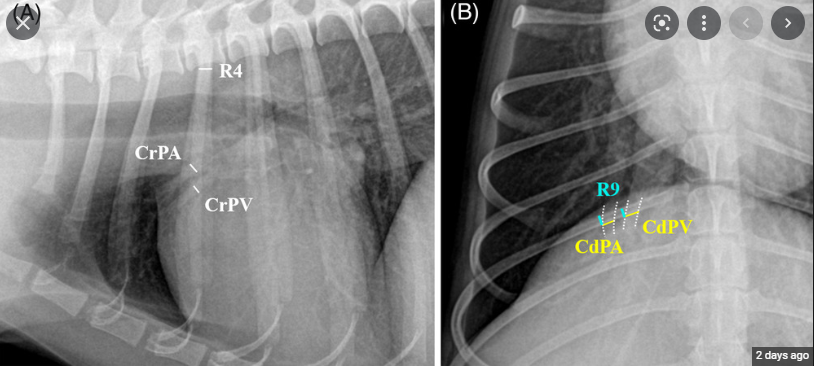

반려견에서 폐 후엽의 폐동맥 크기를 이용한 폐동맥고혈압 추정

폐 전엽, 후엽으로 주행하는 폐동맥과 폐정맥간 비율을 가지고 폐동맥 고혈압 상태를 추정할 수 있는가에 대한 논문이고

결론은 폐 후엽의 비율이 폐동맥 고혈압 상태와 유의적이었다는 논문이다.

컷오프를 1.1로 잡았을때 특이도가 90.6%이니 유의적이나